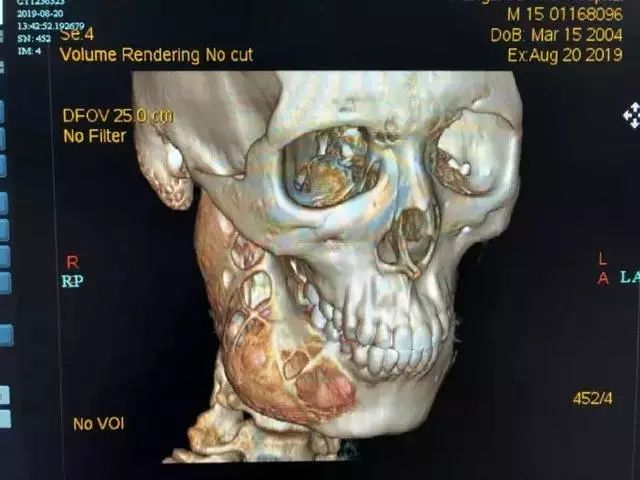

可就在上周,牙疼的程度已经进展到让小莫难以忍受。在家人的陪同下,他来到了杭州市第一人民医院。本以为是简单的牙痛,可令所有人没想到,颌骨3D-CT显示,颌骨被病变“吃掉”了二分之一,里面空了一个“大窟窿”,也就是说,右侧下颌骨体连同整个升支部存在大范围的骨质破坏。

影像检查发现一侧颌骨被肿瘤侵蚀

脸部的骨头被“吃”了一半